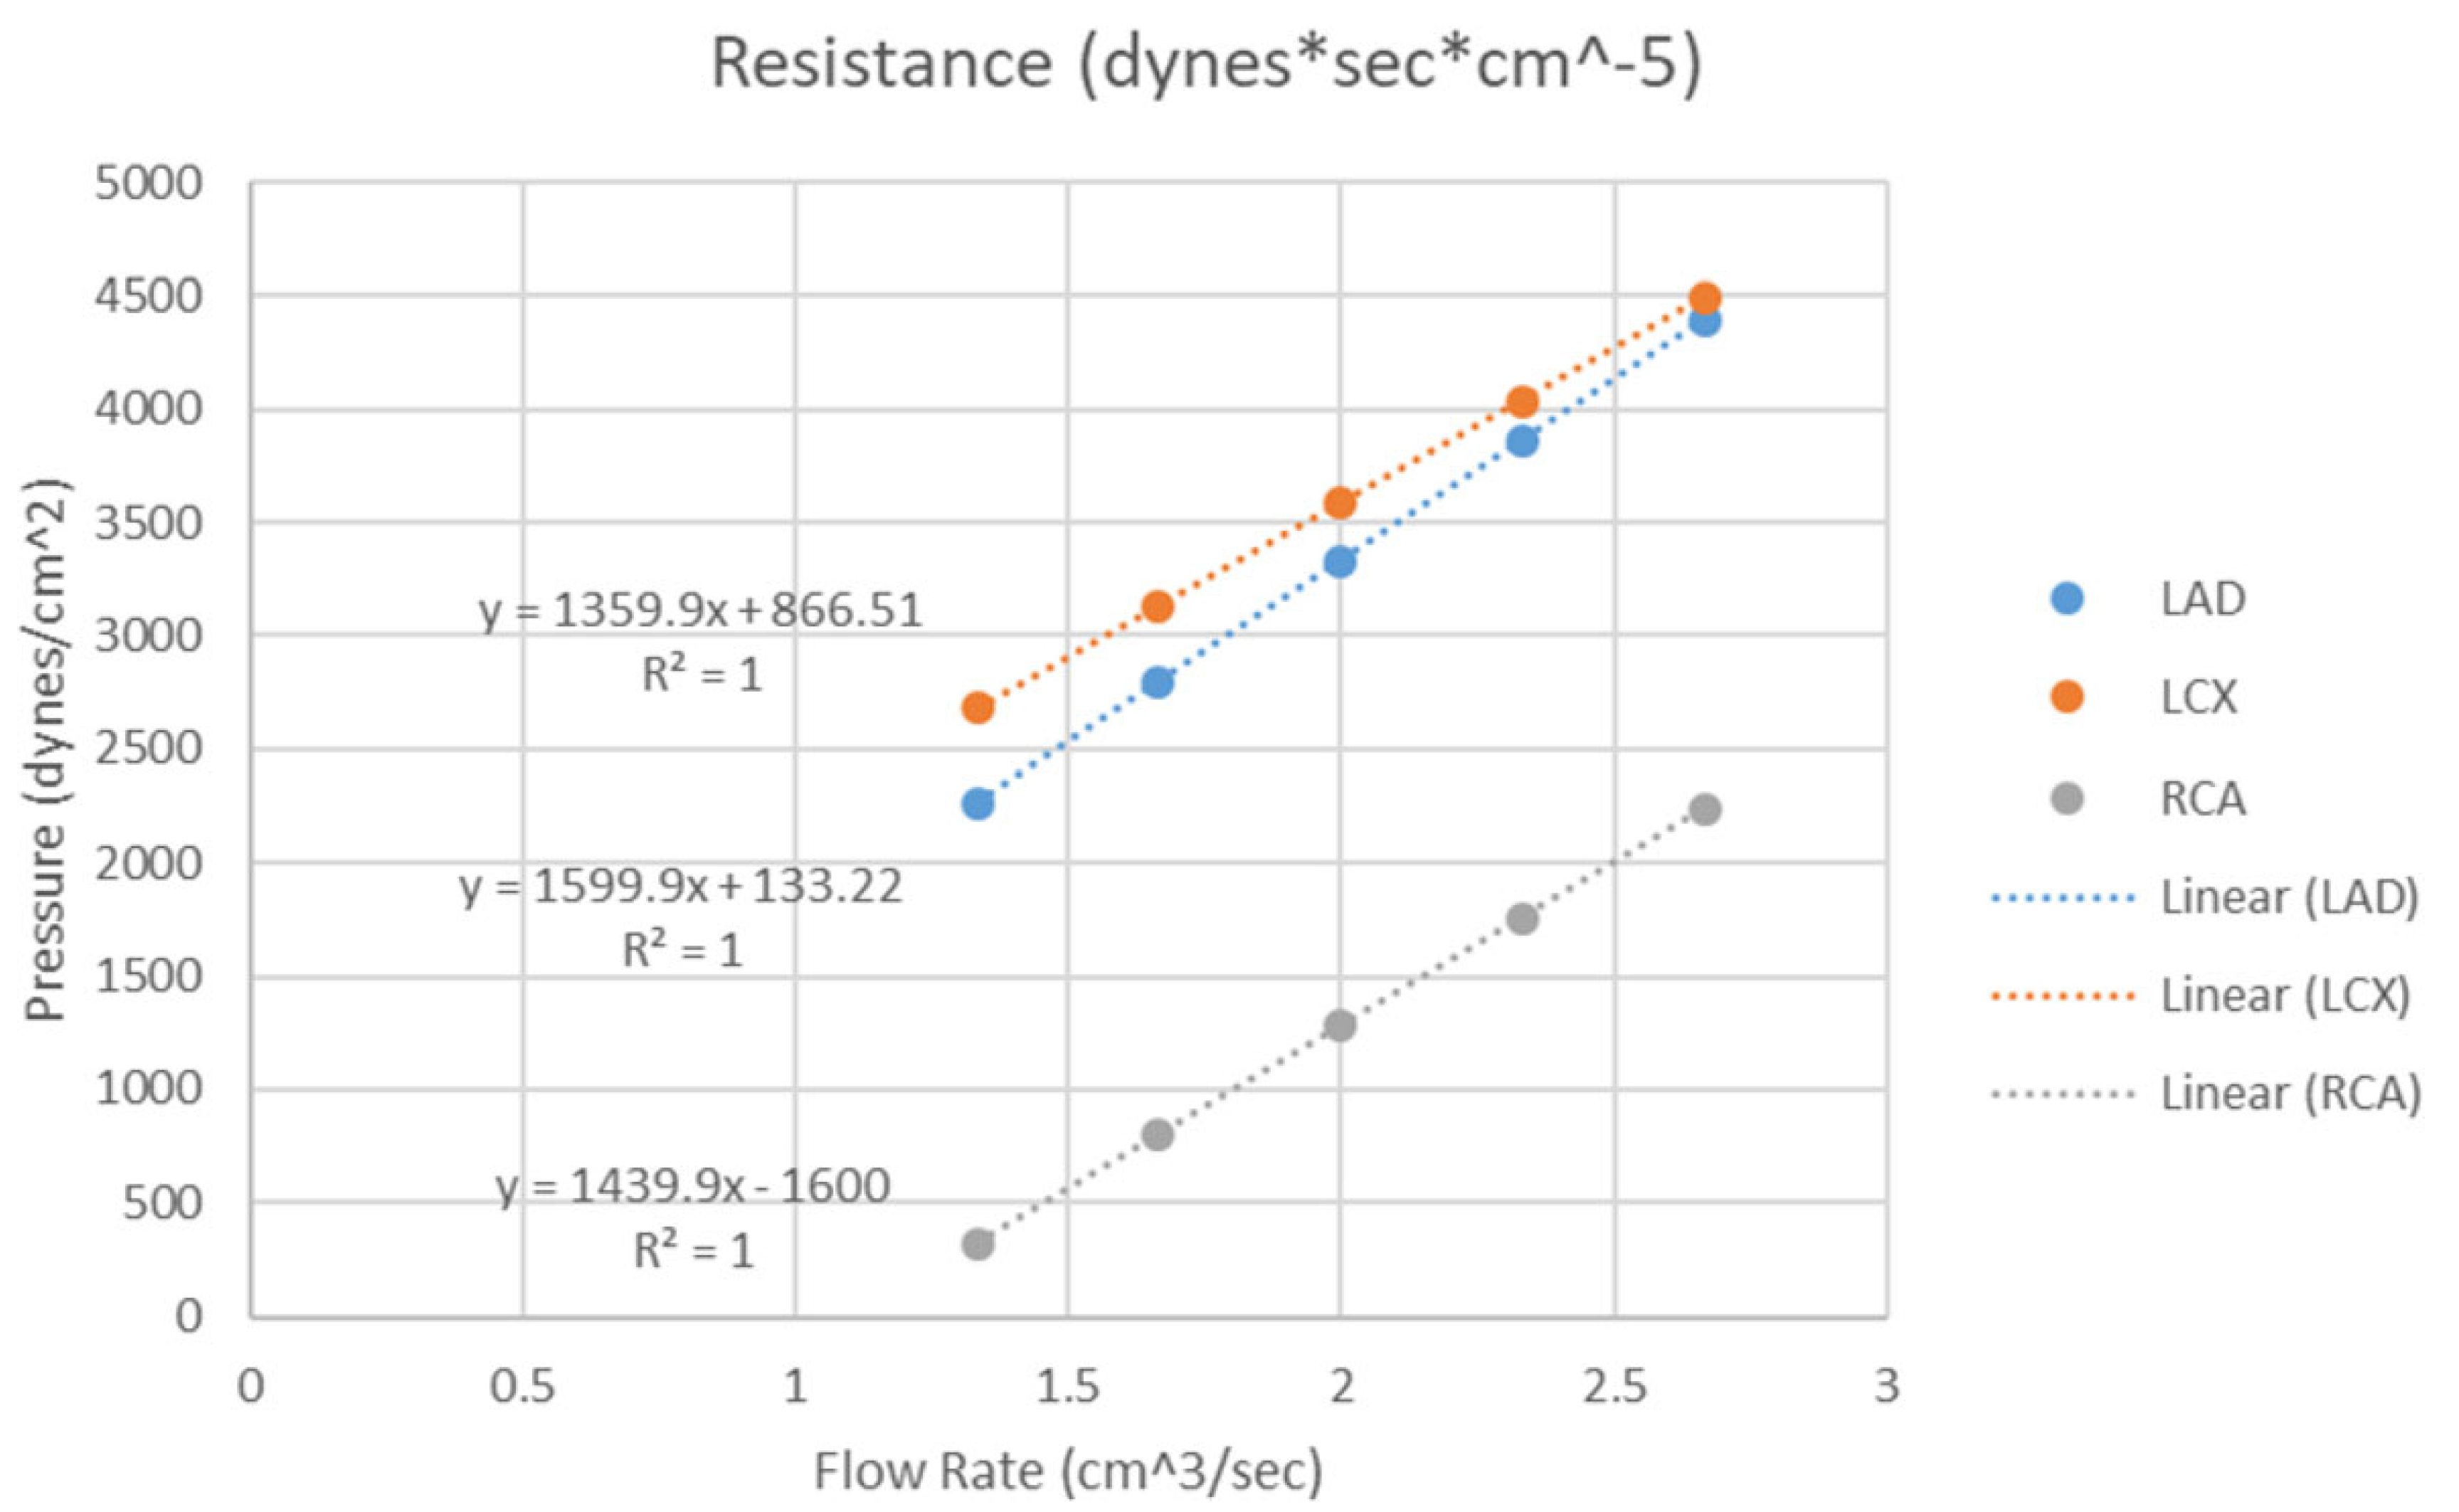

3.3. 3D Printing in Coronary Artery Disease

- Sommer, K.N.; Lyer, V.; Kumamaru, K.K.; Rava, R.A.; Ionita, C.N. Method to simulate distal flow resistance in coronary arteries in 3D printed patient specific coronary models. 3D Print. Med. 2020, 6, 19. [Google Scholar] [CrossRef] [PubMed]